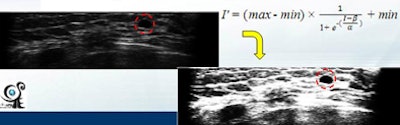

"Images are preprocessed by removing black regions, subsampling to reduce the detection time, and sigmoid filtering to enhance the boundary between tumor and normal tissue," Chang said. "A 3D fuzzy technique is adopted to detect tumor regions in the breast."

| Images are preprocessed by removing black regions, subsampling to reduce detection time, and sigmoid filtering to enhance the boundary between tumor and normal tissue. |